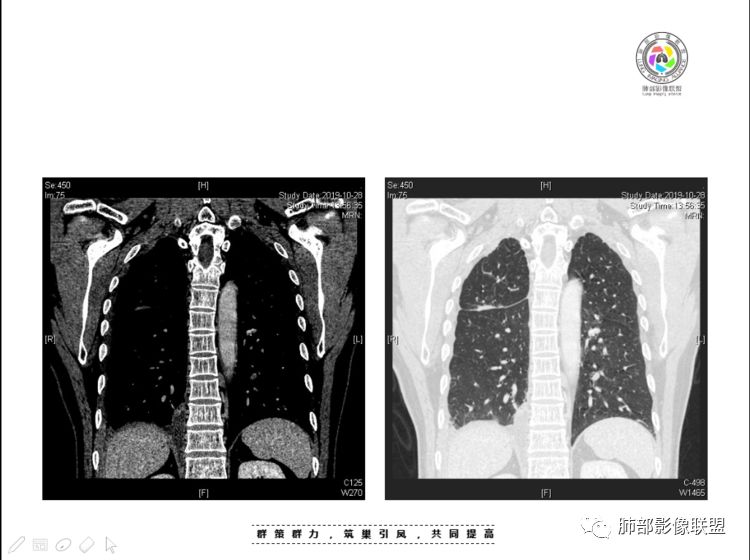

本例纵隔与肺内两处病变,回顾总结分析:

2、前纵隔内病灶囊实性混杂密度病灶,囊性病灶主要位于右侧,张力较高,有分隔影,囊壁右侧缘光整,病灶左侧实性部分边界不清明显强化,病灶肺瘤交界面大部分边界清楚,部分模糊。

纵隔内病灶不符合肺癌转移途径,且纵隔内单发的囊实性转移罕见。淋巴瘤无论是分布、形态、密度、还是强化方式度不符合。

患者缺乏纵隔炎的临床表现,囊性病损更难以解释。

胸腺瘤/胸腺癌符合吗?

胸腺瘤/胸腺癌:病灶内那么大的囊,常规考虑B型以上胸腺瘤,囊内有分隔影,病灶周围脂肪间隙模糊,常规考虑侵袭性胸腺瘤或胸腺癌,若侵袭性胸腺瘤,常侵犯胸膜、心包,很少累及肺。胸腺癌易侵犯胸膜、肺并纵隔淋巴结及远处转移。但肺内腺癌形态更符合原发灶。胸膜及叶间裂转移则即可来自肺,也可来自胸腺癌。

尽管前纵隔病灶缺乏相关病理资料,但是小编还是认为肺内与纵隔病灶以二元论解释。只是肺内恶性病灶引发的胸膜改变可能会影响我们对纵隔病灶的判断。